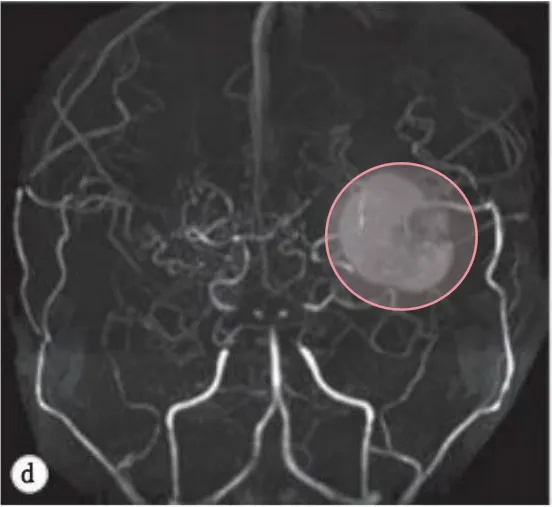

二次手术一年半后,在一次常规随访中,MRI发现左侧岛叶有一个小病变如图3a。复查脑MRA显示在左侧MCA远端有一个动脉瘤等圆形病变(图3b),然而,进一步的DSA检查排除了一个动脉瘤(图3c)。排除了脑内血肿或海绵状血管瘤等其他诊断病因可能,但由于桃子暂无无症状,暂时选择了保守治疗,包括减少阿司匹林剂量(2.5mg/5kg/天)。

图3.轴向(a)和冠状(b)T2加权磁共振图像显示左侧岛叶皮质有一个小的圆形混合强度质量(箭头)。c体积渲染磁共振血管造影。在大脑中动脉的左远端(箭头)发现一个浆果状病变,留下大动脉瘤的印象。d数字减影血管造影的动脉期。左侧颈内动脉造影术未发现动脉瘤等异常表现。

在我们的病例中,在血管重建手术半年复查DSA显示烟雾血管消退(图2),但发现血肿扩大后重复DSA显示基底神经节毛细血管再增生。实际上,CD34/EVG染色的病理标本显示有大量的微血管。